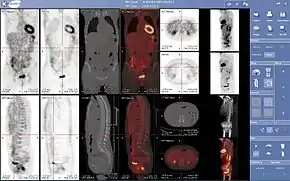

PET scanners can incorporate a CT scanner and are known as PET-CT scanners. PET scan images can be reconstructed using a CT scan performed using one scanner during the same session.

Oncology

PET scanning with the tracer 18F-FDG is widely used in clinical oncology. FDG is a glucose analog that is taken up by glucose-using cells and phosphorylated by hexokinase (whose mitochondrial form is significantly elevated in rapidly growing malignant tumors). Metabolic trapping of the radioactive glucose molecule allows the PET scan to be utilized. The concentrations of imaged FDG tracer indicate tissue metabolic activity as it corresponds to the regional glucose uptake. 18F-FDG is used to explore the possibility of cancer spreading to other body sites (cancer metastasis). These 18F-FDG PET scans for detecting cancer metastasis are the most common in standard medical care (representing 90% of current scans). The same tracer may also be used for the diagnosis of types of dementia. Less often, other radioactive tracers, usually but not always labelled with fluorine-18, are used to image the tissue concentration of different kinds of molecules of interest inside the body.

A typical dose of FDG used in an oncological scan has an effective radiation dose of 7.6 mSv.[3] Because the hydroxy group that is replaced by fluorine-18 to generate FDG is required for the next step in glucose metabolism in all cells, no further reactions occur in FDG. Furthermore, most tissues (with the notable exception of liver and kidneys) cannot remove the phosphate added by hexokinase. This means that FDG is trapped in any cell that takes it up until it decays, since phosphorylated sugars, due to their ionic charge, cannot exit from the cell. This results in intense radiolabeling of tissues with high glucose uptake, such as the normal brain, liver, kidneys, and most cancers, which have a higher glucose uptake than most normal tissue due to the Warburg effect. As a result, FDG-PET can be used for diagnosis, staging, and monitoring treatment of cancers, particularly in Hodgkin lymphoma,[4] non-Hodgkin lymphoma,[5] and lung cancer.[6][7][8]

PET imaging has been used for imaging muscles and bones. 18F-FDG is the most commonly used tracer for imaging muscles, and NaF-F18 is the most widely used tracer for imaging bones.

Together with NaF-F18, PET for bone imaging has been in use for 60 years for measuring regional bone metabolism and blood flow using static and dynamic scans. Researchers have recently started using NaF-18 to study bone metastasis[37] as well.

Combination of PET with CT or MRI

PET scans are increasingly read alongside CT or magnetic resonance imaging (MRI) scans, with the combination (called "co-registration") giving both anatomic and metabolic information (i.e., what the structure is, and what it is doing biochemically). Because PET imaging is most useful in combination with anatomical imaging, such as CT, modern PET scanners are now available with integrated high-end multi-detector-row CT scanners (so-called "PET-CT"). Because the two scans can be performed in immediate sequence during the same session, with the patient not changing position between the two types of scans, the two sets of images are more precisely registered, so that areas of abnormality on the PET imaging can be more perfectly correlated with anatomy on the CT images. This is very useful in showing detailed views of moving organs or structures with higher anatomical variation, which is more common outside the brain.